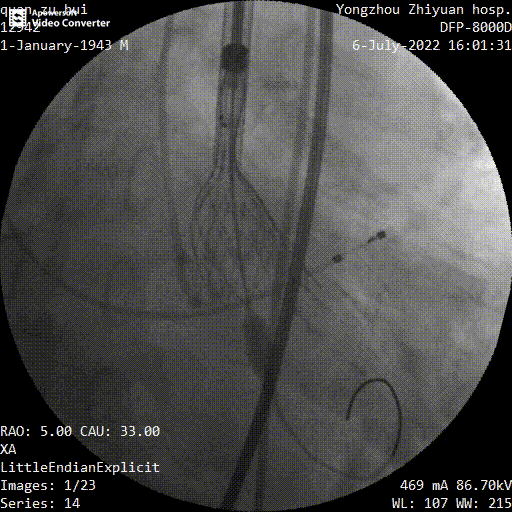

瓣膜定位

最终释放

手术过程中,在完成跨瓣操作后,23mm球囊预扩有轻微腰征、无造影剂渗漏,预装TaurusElite AV29瓣膜到位,输送系统快速、顺利地完成过弓、跨瓣操作,于瓣环上约2mm定位释放;针对本例患者瓣叶明显增厚伴重度钙化,左右窦间可见钙化融合嵴的特点,TaurusElite瓣膜高密度流入端设计提供了足够的径向支撑力,保证了瓣膜的锚定力,瓣膜内外双裙边设计能提供良好的辅助锚定力,有效减少瓣周漏。此外,本例患者左窦间存在长条状钙化延伸至瓣环下10mm水平,释放位置偏深可能存在起搏器植入风险,TaurusElite瓣膜具有多次完全可回收,回收后可重新跨瓣、释放的特点,给予术者足够的信心完成高位释放的操作,释放后最终瓣架底端位于瓣环下约1mm,实现了释放位置的精准控制,有效的减少了起搏器植入风险,确保了手术安全、顺利的完成。这例手术为永州地区开展的第一台TAVR手术,填补了该地区TAVR技术空白,标志着永州市心脏瓣膜疾病诊治迈入了全新的微创治疗时代!